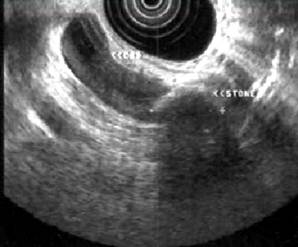

Рисунок 2 – Эндосонография: А – норма, Б – Холедохолитиаз: резко расширенный

холедох, визуализируется конкремент